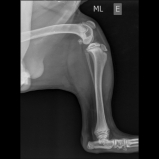

Cada vez mais cães e gatos tem feito parte da vida das nossas vidas e muitas vezes são vistos como mais que animais de estimação e sim como membros das famílias. Esse membro da sua família merece o melhor em exames laboratoriais para animais. A Amazing Pets oferece os mais tecnológicos e modernos exames laboratoriais para garantir a saúde de seu animal. Com muita rapidez, fornece os resultados dos exames que dirão qual o melhor tratamento para as doenças de seus bichos de estimação. Com exames de hematologia, tomografias, raio-x, entre outros, a Amazing fornece um diagnóstico rápido para curar as patologias que acometem seu animal.